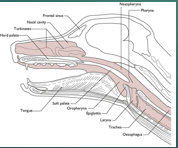

Upper respiratory tract

Nasal passages

Sinus

Pharynx

Larynx

Lower respiratory tract

Trachea

Bronchi

Bronchioles

Lung Parenchyma - Interstitial and alveolar spaces